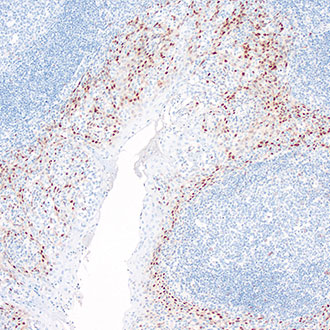

CD8

CD8 -